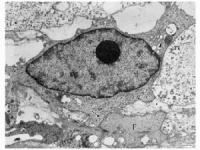

脊索瘤表现为光滑性结节肿瘤组织为白色半透明胶冻状含大量黏液伴广泛出血时呈暗红色。瘤体边缘常呈分叶状或结节状,表面有一层纤维组织包膜一般不穿破进入邻近脏器。镜下见肿瘤细胞较小,立方形、圆形或多角形,胞膜清楚胞质量多红染常见空泡,空泡大者可达到一般细胞体积的几十倍,即所谓“大空泡细胞”。胞核圆形或卵圆形,位于中央。细胞排列成索条状或不规则腺腔样期间为黏液偶见核大深染细胞、多核细胞和核分裂细胞。